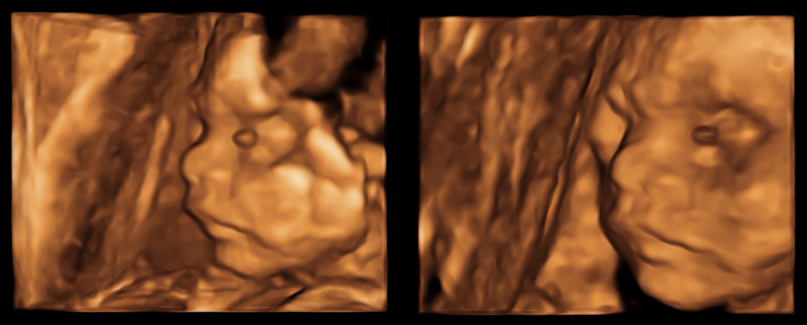

Well! What a journey it has been so far especially with Covid restrictions but it’s been an amazing one at that! Firstly, at the time of writing this, January ‘22, I am currently 16 weeks pregnant through my Success program on the first IVF attempt. Secondly, don’t feel hesitant in asking too many questions even the ones that may sound irrelevant or small, all questions are valid and Success have been very helpful and response during the first part of my Success journey. It made my decision easy in choosing Success to make my dreams come true in becoming a father. I am excited and looking forward to the next part of my journey with Success and look forward to updating you all later in the year when I become a father in June ‘22. Success can make your dreams come true like they have for me as I am PREGNANT.